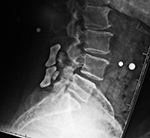

Lumbar spine bony disk strut, pedicle screws, and pedicle rods (lateral view) |

20 year-old woman with L1 vertebral body compression fracture treated with T12-L2 posterior spinal fusion using pedicle screws at T12 and L2 with connecting rods on each side. |